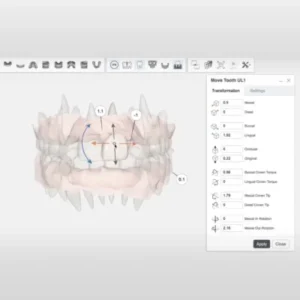

ทันตแพทย์จะใช้ซอฟต์แวร์ที่ขับเคลื่อนด้วย AI วิเคราะห์และวางแผนการเคลื่อนที่ของฟันแต่ละซี่อย่างละเอียด เพื่อคำนวณทิศทาง, การใช้แรง, และเวลาที่เหมาะสมให้ฟันเคลื่อนไปยังตำแหน่งที่ต้องการ

วางแผนการรักษา ด้วย AI Technology และ 3D Computer Imaging